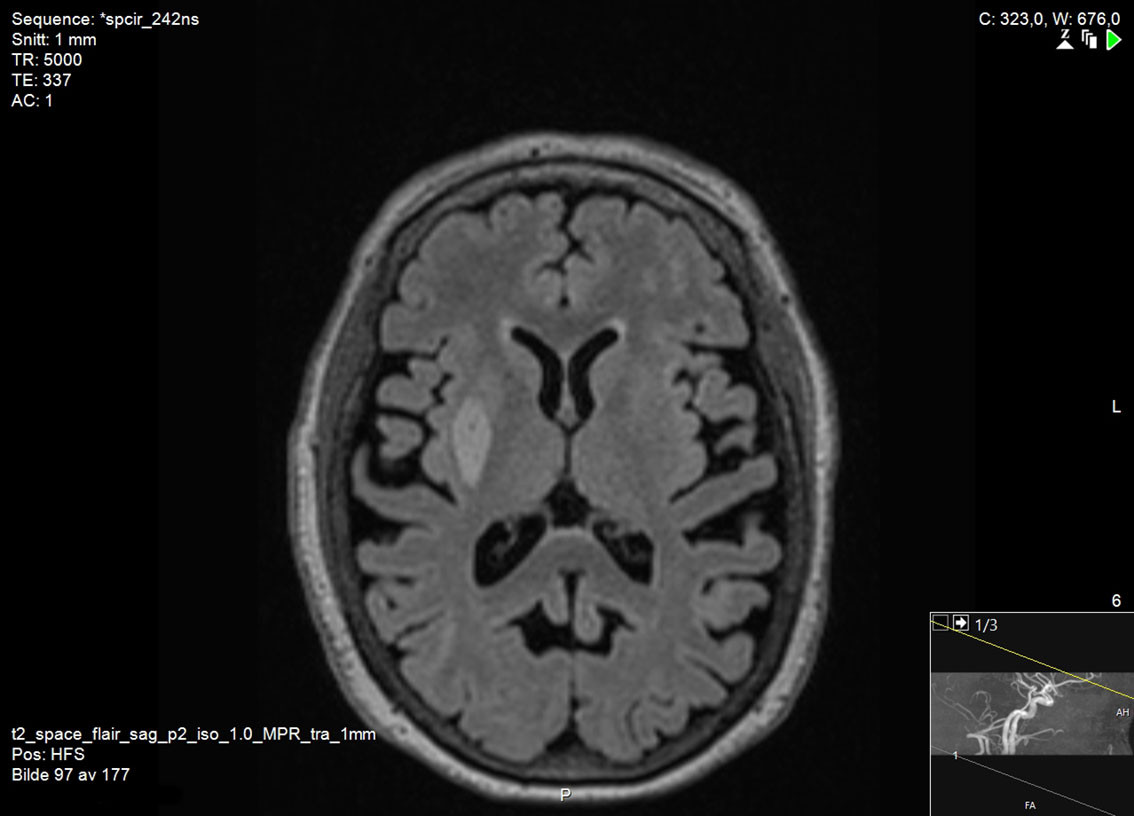

There are no universally accepted guidelines for the diagnosis of vascular parkinsonism, but based on clinical findings and pathology, Zijlmans et al. have proposed the following criteria: a) parkinsonism, b) cerebrovascular disease visible on MRI or CT, and c) a relation between a) and b), either in the form of acute hemiparkinsonism resulting from infarction or haemorrhage in the nigrostriatal pathway (subtype 1), or small vessel disease in the white matter with gradual development of parkinsonism (subtype 2) (15). Typically, brain MRI is necessary to determine whether there is damage to the nigrostriatal pathway (Figure 1) or small vessel disease in the white matter (Figure 2). CT scans of the brain are less suitable for making the diagnosis due to their lower sensitivity for lacunar infarcts and small vessel disease (5).

Differences between vascular parkinsonism and Parkinson's disease are also seen on brain imaging. In cases of vascular parkinsonism, brain MRI will reveal infarction, haemorrhage, or signs of small vessel disease. In Parkinson's disease, brain MRI can appear completely normal, although elderly patients may have vascular changes as incidental findings; however, these will be much less abundant than in cases of vascular parkinsonism (20, 21). A dopamine transporter scan (DaTSCAN) is a nuclear medicine procedure that shows changes in brain dopaminergic activity, and that can be used to detect degeneration of nigrostriatal nerve endings. DaTSCAN always shows pathological changes in Parkinson's disease, whereas in cases of vascular parkinsonism DaTSCAN is often normal if the nigrostriatal pathway is not directly affected (5).